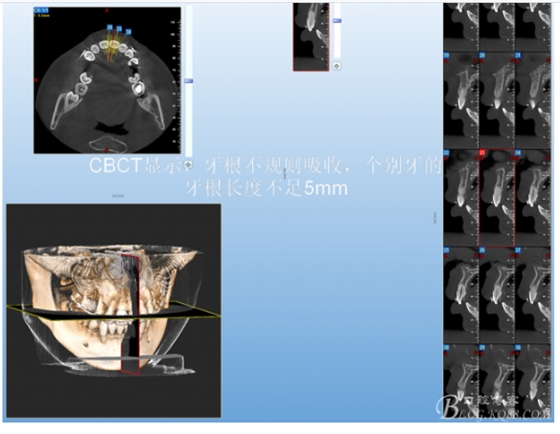

有15%的人在正畸治療前就已經(jīng)發(fā)生牙根吸收,這與激素失衡和飲食缺乏有關(guān)。正畸治療后12個月,牙根再吸收的發(fā)生率增加到73%,有25%的正畸治療患者根尖吸收超過2mm,約5%的人發(fā)生超過5mm的嚴(yán)重吸收。

大多數(shù)研究認(rèn)同牙根再吸收的嚴(yán)重性與正畸治療的持續(xù)時間、力量大小相關(guān)。臨床醫(yī)師應(yīng)該采用輕力、高效的矯治手段進行正畸治療,并在正畸治療前、中、后進行X線檢查對比,觀察牙根再吸收的發(fā)生情況。研究發(fā)現(xiàn):間斷治療的患者其牙根再吸收量明顯少于那些持續(xù)治療的患者。應(yīng)用力的中斷有助于已破壞的牙周組織重建并減少牙根的進一步縮短。